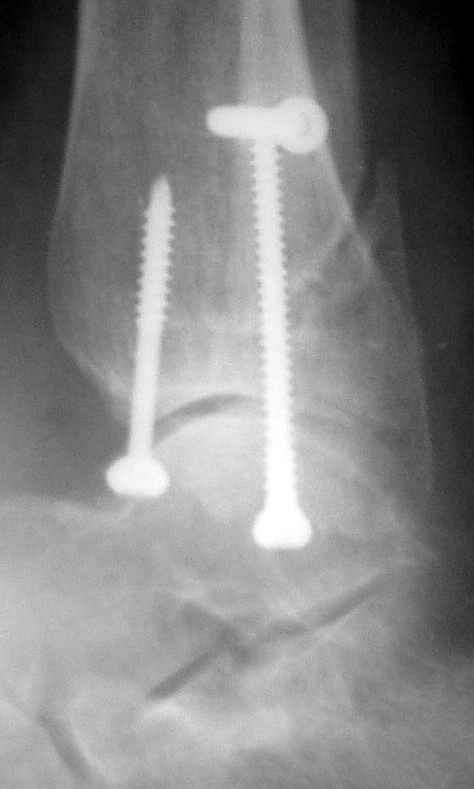

До операции 28 июля

Операция 29 июля